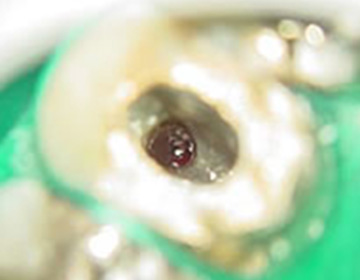

根管治療では、 汚染された根管 内を完全に洗浄し、痛みを除去し、

違和感なく自然に噛めるまで確実に回復する治療を行います。

CT撮影、麻酔後、ラバーダム防湿を行って根管治療を開始します。

噛み合わせが狂わないよう、歯の周りは残して根管治療を行います。

根管内の汚染物質、汚染資質を取り除き、痛みが取れるまで、徹底的に洗浄します。根管内に貯まったエネルギー調整も同時に行います。

複雑な根の細部にまで材料が入るように特殊な装置で根管を行います。

痛み、レントゲン検査による治療結果の判定。